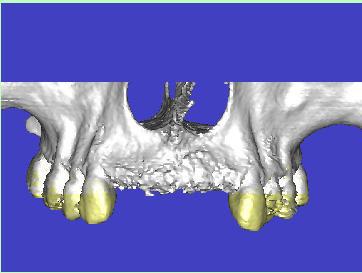

les gars je rentre chasse canards peut être ai je un peu abusé mais vous les prenez ou les lambeaux and co vs avez vu le scan a droite çà me parait difficile et a gauche pas cool sur un site d'ex°

Scanner de contrôle quelques mois plus tard...

Preservation de crete - Eugenol

la procédure a permis de conserver le volume osseux disponible voir même l'augmenter, la difficulté est que le produit de comblement est radio-opaque et que sa cohésion est délicate à aprécier. peut -tu faire part de tes sensations lors du forage.